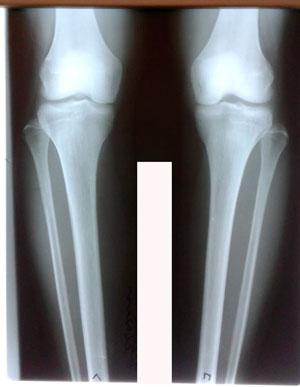

Исходник - 28 лет.

Дата операции - 04.06.2020

До круток